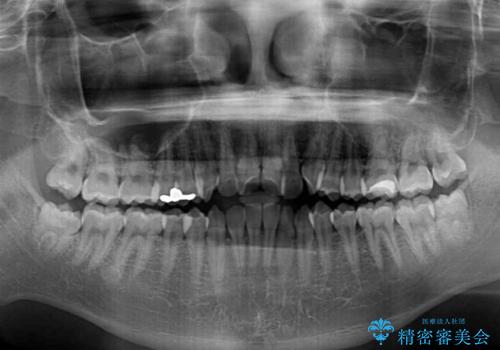

- 上下前歯のデコボコを気にして来院された患者様です。

ワイヤー矯正でもマウスピース矯正でも可能でしたが、短期間で、自身の手を煩わせることなく治療を行いたいとのことで、ワイヤー装置にて矯正治療を行うこととしました。

当初予定通り、1年間で治療を終えることができました。